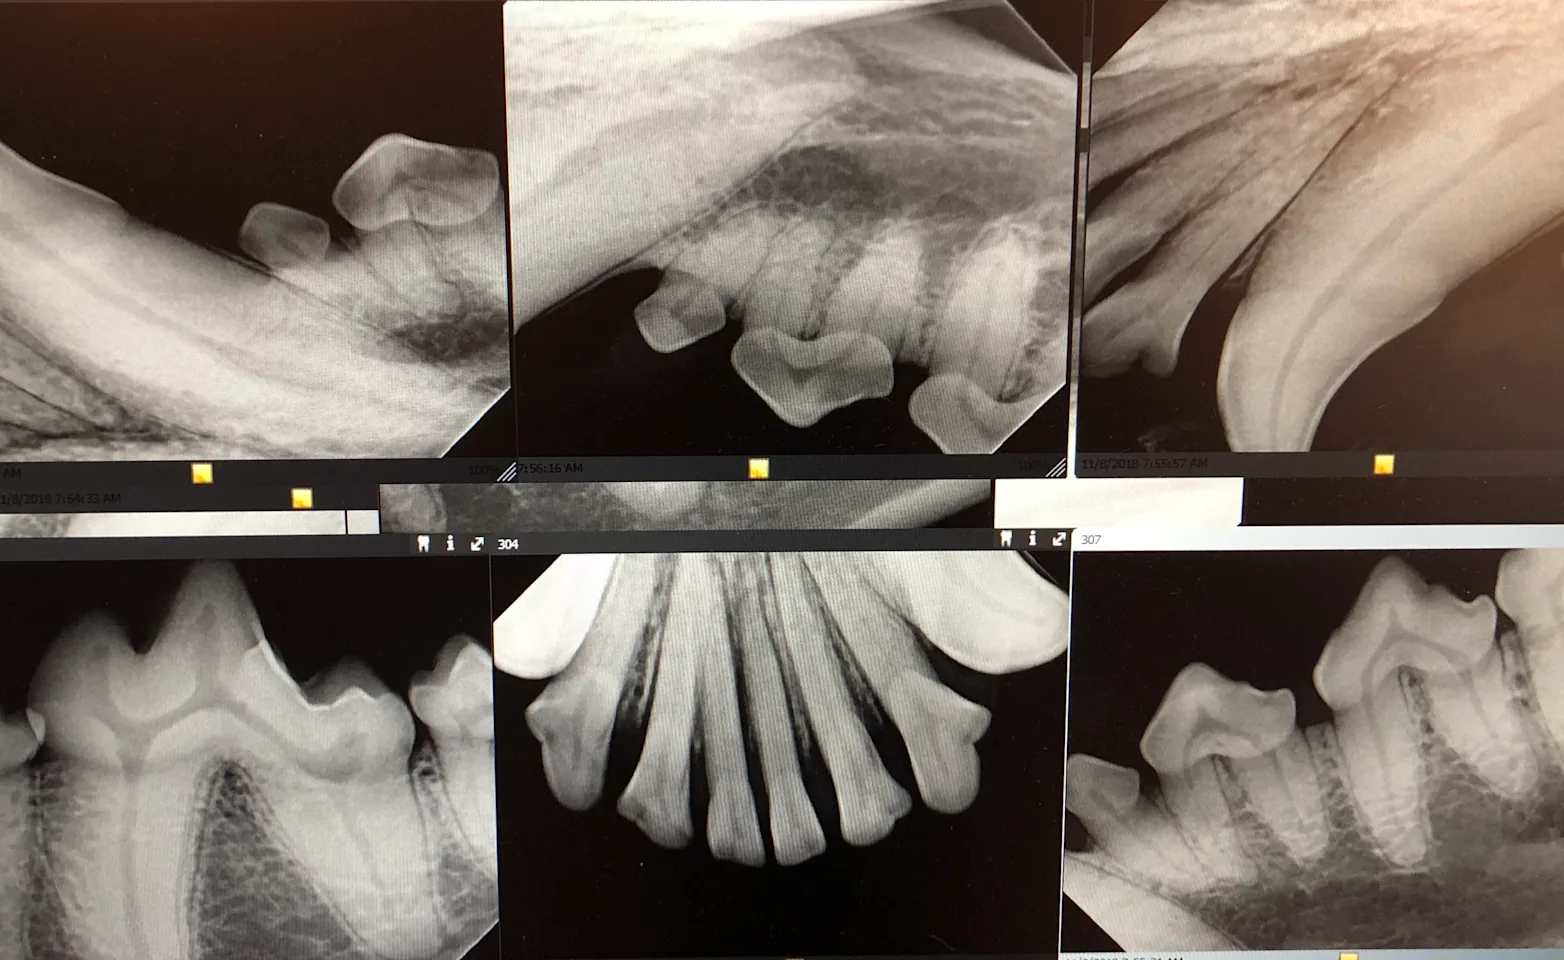

Each tooth is examined, evaluated, cleaned with the ultrasonic scaler, polished, and x-rayed to assess health under the gumline as well. The veterinarian evaluates the x-rays to determine if any extractions are needed.